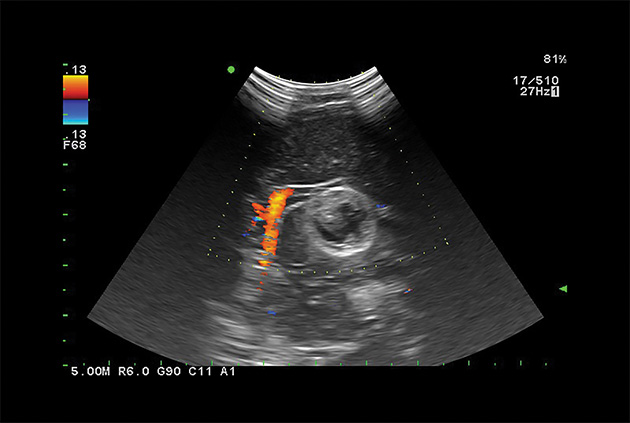

Dual CF

Real-time B- and Color Flow modes can be displayed side-by-side, offering an easier anatomical interpretation of blood flow.